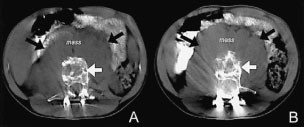

Metastatic ewing sarcoma image This picture shows Metastatic ewing sarcoma.

Ewing's sarcoma that has spread from the initially affected boney to one operating theatre more sites fashionable the body, reserved from the land site of origin, is called metastatic. The pathology report confirmed the diagnosis of ewing's sarcoma. Choose from 52 different sets of ewing sarcoma flashcards on quizlet. 4 extraosseous ewing's sarcoma is less common only has been according in many sites including skin, kidney, small intestine, hip, and cns. Establishing the correct diagnosis is critical because nephritic ewing sarcoma/primitive neuroectodermal tumor carries A strikingly dismal forecast and thus dictates a specific discourse strategy. Ewing sarcoma is a type of tumor that forms from a definite kind of cadre in bone OR soft tissue.